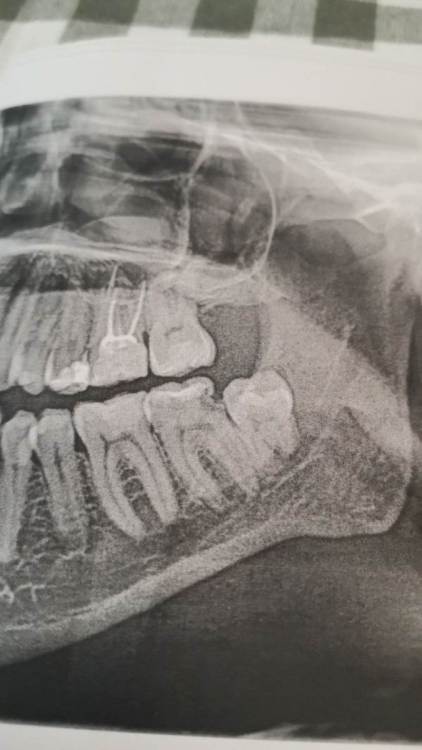

lightman Опубликовано 24 декабря, 2023 Поделиться Опубликовано 24 декабря, 2023 Всех приветствую. После удаления левой нижней восьмерки (лежала частично в кости, разрушала соседний зуб и смотрела в язычную сторону) не отошла анестезия с левой стороны языка, примерно 2/3 его части. Написал на следующий день об этом врачу и был поставлен диагноз - парестезия. Первое время язык был совсем деревянный и даже испытывал трудности в общении. Также было небольшое чувство жжения и лопающихся пузырьков где то ближе к кончику, помимо этого беспокоило повышенное слюноотделение. Спустя 3 недели беспокоит больше всего слюноотделение и странное чувство, будто что то натягивается в левой части языка, когда вытягиваю вперед нижнюю челюсть или широко открываю рот. Очень неприятные ощущения, но не болезненные. Все остальное больше практически не испытываю. Если надавить посильнее в левой части, то чувствую тупую боль где то внутри языка, но не могу с уверенностью сказать, что не испытывал этого и в первое время после удаления, так как не проверял. Может кто нибудь подскажет - что это может там так натягиваться, что даже чувствую это с не работающей стороны языка? Лечащий врач на этот вопрос ответа не дал. Также на счет слюноотделения - это нормально при травме язычного нерва? Потому что много читал жалобы людей на подобные случаи, но никто не писал про повышенное слюноотделение. По мнению врача, парестезия возникла в следствии инъекции анестезии. Во время удаления один раз было чувство прострела где то под зубом, но в это время врач говорит, что доставал корни и повредить нерв не мог. Также врач сказал, что подпиливал примерно на 2 мм стенку с язычной стороны. И еще момент, рассматриваю заранее самые негативные сценарии - хроническая потеря чувствительности. И поэтому хотел бы узнать, может кто нибудь изучал вопрос - есть ли в России какие нибудь центры или отдельные специалисты, которые занимаются восстановлением таких нервов? Пью только мильгамму. Спустя удаления прошло 3 недели на момент создания темы. На всякий случай приложил фото зуба до операции. Ссылка на комментарий